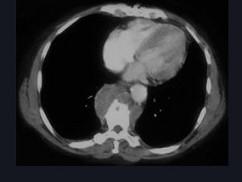

问题 女,34岁,发热,背部疼痛1个月余,请结合影像学检查,选出最可能的诊断 ( )

选项 A、脊椎转移瘤 B、骨髓瘤 C、脊椎结核 D、骨髓炎 E、椎体压缩骨折

答案 D